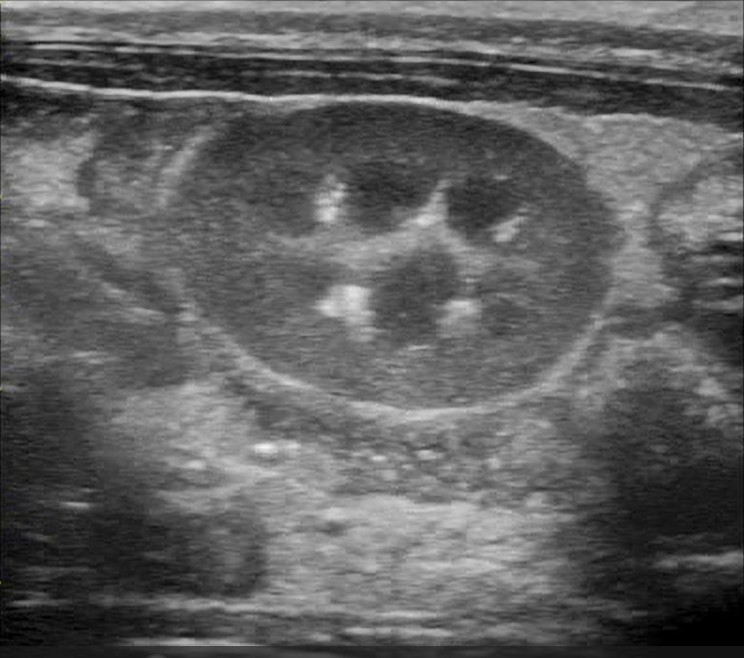

超音波検査

ウサギの腎不全において、超音波検査は、腎臓の大きさに加え、X線検査では評価が困難な腎実質の内部構造、皮質と髄質の境界、腎盂の状態、さらには血流(ドップラー使用時)を評価するために不可欠な診断ツールです。CRFが進行すると、腎臓は線維化や組織の萎縮により縮小(腎萎縮)し、正常より小さくなることがあります 。また、腎臓の辺縁が不整になり、ゴツゴツとした輪郭を呈することがあります 。間質の線維化、尿細管変性、鉱質沈着(石灰化)などが起こると、腎実質(特に皮質)のエコー輝度は上昇し、周囲の脾臓や肝臓と比較して白っぽく見えます 。急性腎不全では、浮腫や炎症の程度によってエコー輝度が低下することもあります 。正常なウサギでは、皮質(やや低エコー)と髄質(より低エコー)の境界は比較的明瞭に描出されます 。慢性腎不全で線維化や実質の構造破壊が進行すると、この皮質・髄質境界は不明瞭になります 。腎石灰化によるカルシウム沈着は、高エコー輝度の斑点や線状構造として描出され、強い音響陰影を伴うことがあります。また、水腎症では腎盂内部が無エコーの尿で拡張する一方、腎盂膿瘍では無エコーよりエコー輝度が高い膿によって拡張します。腎実質内に辺縁明瞭な無エコー領域(嚢胞)が単発性または多発性(多発性嚢胞腎)に見られることもあります 。腎臓腫瘤は、腎臓の形状不整、実質の不均一なエコーパターン、あるいは正常構造を破壊する腫瘤(例:リンパ腫によるびまん性の高エコーまたは低エコー浸潤)として観察されることがあります。